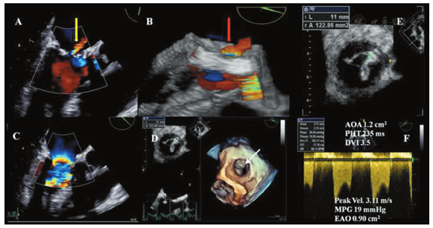

正确区分血栓形成和血管翳过度生长仍然具有挑战性。近期出现的呼吸困难或血栓栓塞事件和有抗凝治疗未达标病史者,提示为瓣膜血栓形成导致的梗阻。血栓通常是活动的、呈球形,超声显示为低回声(与心肌组织回声相似),可能附着于瓣膜阀体或缝合环上(图9)。血管翳是固定不活动的,超声显示为强回声(小的致密团块,与瓣膜罩回声相似),并与瓣膜装置相连(瓣膜罩和瓣轴保护装置)(图10)[124]。由于血管翳可诱发血栓形成,其诊断更加困难。心脏CT检查显示血栓的CT衰减值低于血管翳,建议以200 HU作为二者鉴别的阈值(表10)[54,62]。

应显示主动脉瓣PHV的所有部分,包括缝合环、瓣叶、瓣膜支架、阀体及周围组织。超声心动图是首选的检查手段,但当超声心动图不能明确诊断时,则可应用荧光透视成像、心脏CT、CMR等检查手段[15,21,29,41,50,64]。TTE检查时必须采用所有的标准切面进行检查。应用彩色多普勒显像以明确存在正常的前向血流和显示预期的冲刷血流束[7,14],并排除病理性瓣膜射流束或瓣周射流束。对瓣膜缝合环的全部周长都要进行评价。在胸骨旁长轴、短轴切面和心尖三腔心、五腔心切面仔细观察瓣叶或阀体的运动情况。在胸骨旁长轴切面观察人工生物瓣膜的支架最佳。仔细调整超声束与阀体开口方向平行可降低声束透过瓣膜平面时产生的声影,从而有利于阀体的充分显示,这在从心尖切面观察时更加有效。值得注意的是,在胸骨旁短轴切面显示人工瓣AR的起源处(中央性或瓣周性)最佳。然而,由于人工瓣膜支架声影的遮挡,位于后方的瓣周性反流束在胸骨旁长轴切面或短轴切面观察时往往全部或部分被声影遮挡。因此,需要利用心尖切面仔细探测以发现并定量评价位于后方的反流束。TOE检查时,参考切面定位于食管中段水平,旋转角度至大约45°和120°以分别获得主动脉瓣的短轴和长轴切面,显示主动脉瓣的开放、关闭或阀体的运动以及是否存在AR[15,137]。长轴切面(TTE和TOE)有利于显示LVOT、主动脉瓣环,主动脉瓣叶、Valsalva窦、窦-管交界处及升主动脉起始段。TOE经深部胃底切面、在0° 时的图像亦用于评价LVOT、人工瓣及主动脉近心端。TOE检查时,某些切面存在的声影现象导致位于前面的反流束被漏检或被低估。位于主动脉瓣PHV侧面或中间部位的反流束,在TTE和TOE标准切面上往往难以显示,需要采用离轴/中间切面以显示这些血流束。3D超声心动图,特别是当与TOE相结合时,是全面显示人工主动脉瓣、全部缝合环和任何瓣周漏的理想方法(图16)[22,23,24]。

应评价二尖瓣PHV的所有组成部分(缝合环、瓣叶、阀体、周围组织)。TTE是一线影像学检查,而当怀疑或确认存在瓣膜功能异常时则推荐TOE检查[15,21,27,29,137]。如有必要,可辅以荧光透视成像,心脏CT或CMR检查[40,43,65]。TTE检查需从胸骨旁长轴、短轴切面和多角度的所有心尖切面以及离轴切面上扫描整个缝合环、二尖瓣瓣下装置和瓣叶/阀体的运动情况。生物瓣膜的支架在心尖四腔心切面上显示最佳。彩色多普勒显像用于显示正常前向血流、预期的冲刷性血流和病理性反流。声影遮蔽效应可能导致不能良好显示二尖瓣PHV(尤其是机械性瓣膜)的LA侧(图5A,图5B)[88,89]。调整超声束与阀体开放的方向相平行则可改善瓣膜的显示质量。由于肋下切面遮挡效应最小,有助于显示人工瓣瓣周血流。TOE在检出和确定人工瓣MR的位置和机制方面常常优于TTE[149,150,151]。TOE显示LA和二尖瓣反流束更佳,但声影遮蔽效应限制了其对LV的显示(图5C,图5D)。在食管下段四腔心切面,通过旋转探头至二腔心和三腔心切面同时配合前屈、后屈时,反流束显示最佳。如在扇面中央进行适当调整,横向的经胃底短轴切面有助于显示瓣膜/缝合环的整个周长。TTE/TOE的长轴切面用于测量LVOT(见上文),而短轴切面则可确定任何瓣周漏的周向范围。3D超声心动图,尤其是与TOE相结合时,可理想地显示人工二尖瓣全貌、整个缝合环和瓣周反流的程度(图21)。